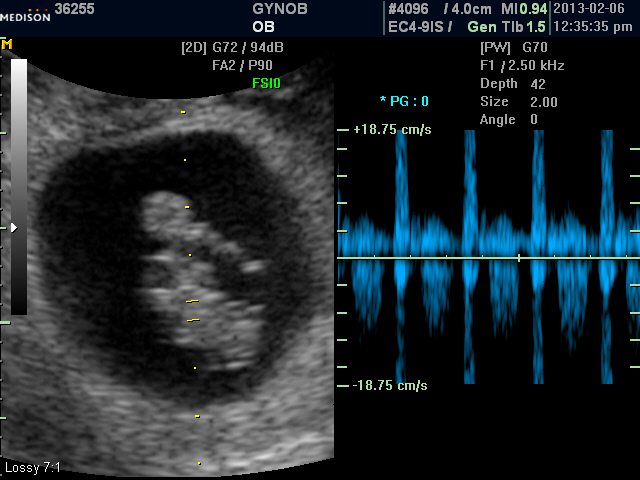

초음파 사진 보니 태아가 8주 정도 된 것 같은데 심장 박동이 확인된 후에는 유산되는 경우는 드물어 너무 걱정하실 것은 없지만 그래도 조심하시기 바랍니다.